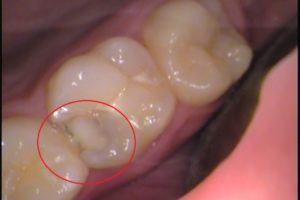

場所はわかりますか?

赤丸で囲まれたココです!

デコボコしているのですが、前に治療した形跡があり、

レジンで詰め物がされています。

その周囲から虫歯が入り込み、2次虫歯になってしまっています。